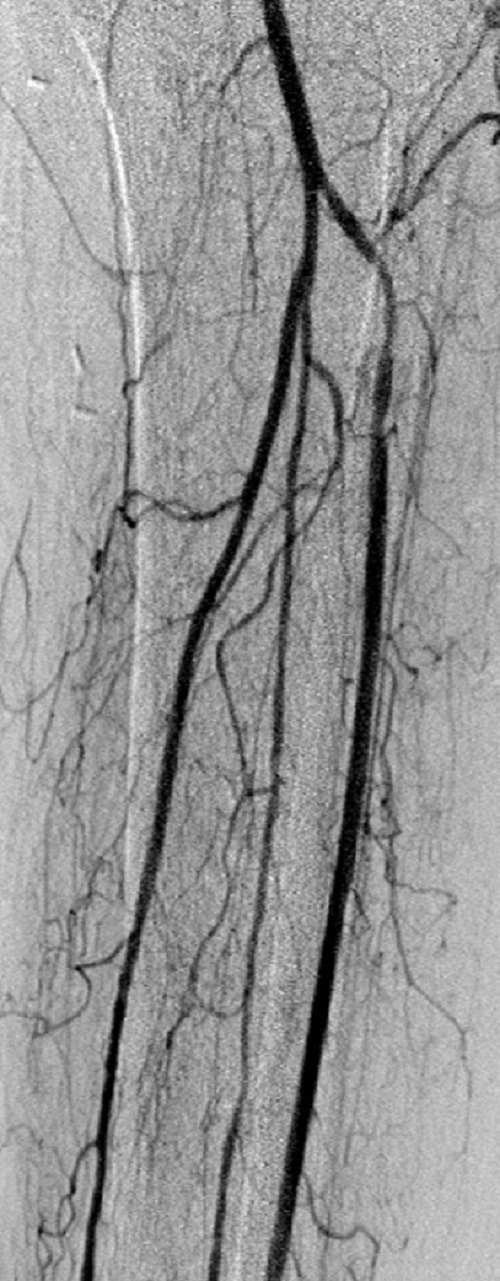

Key to images:

Top panel: Pre-intervention run-off angiogram of the left lower extremity showing, from left to right, irregular left common femoral artery (LCFA) arrowed on the 1st image, absent left superfical femoral artery (LSFA) or any bypass conduit on the 2nd image, sketchy descending collaterals from the left deep femoral (LDFA) that reconstitute a faint shadow of the left popliteal artery, arrowed on the 3rd image. The last 2 images faintly show three-vessel run-off below the left knee. The anterior tibial artery is most opacified, followed by the posterior tibial artery; the peroneal artery peeps through the upper edge of the last image. Note how weakly visible these vessels are due to the poor inflow from above.

When blood flow into or out of a bypass fails, it thromboses and its salvage includes gaining access into it and removing the clot in addition to determining the reason for its failure. Such clot removal may be mechanical, as is frequently the case in acute graft failure, or through thrombolysis, as is the case in later failures. The above images illustrate the later scenario in which the patient presented about 1 year after a left femoropopliteal bypass was fashioned for them. I crossed into the lumen of the bypass conduit from a right common femoral arterial puncture and advanced an infusion cather into it for overnight continuous alteplace infusion following a bolus dose. (I favor 5 to 10 mg of alteplace bolus, followed by continuos infusion at 0.5 mg per hour, in company with fixed unfractionated heparin infusion at 500 units to 600 units per hour after a bolus dose of 3000 units to 5000 units). In this case the bypass proved to be a vein conduit connecting the left common femoral artery, proximally, to the mid popliteal artery, distally, without intimal hyperplasia. The cause of the failure was diminished inflow due to left iliac disease.The final runoff images reveal a three-vessel tibial domain continuous with a near-normal plantar arch.